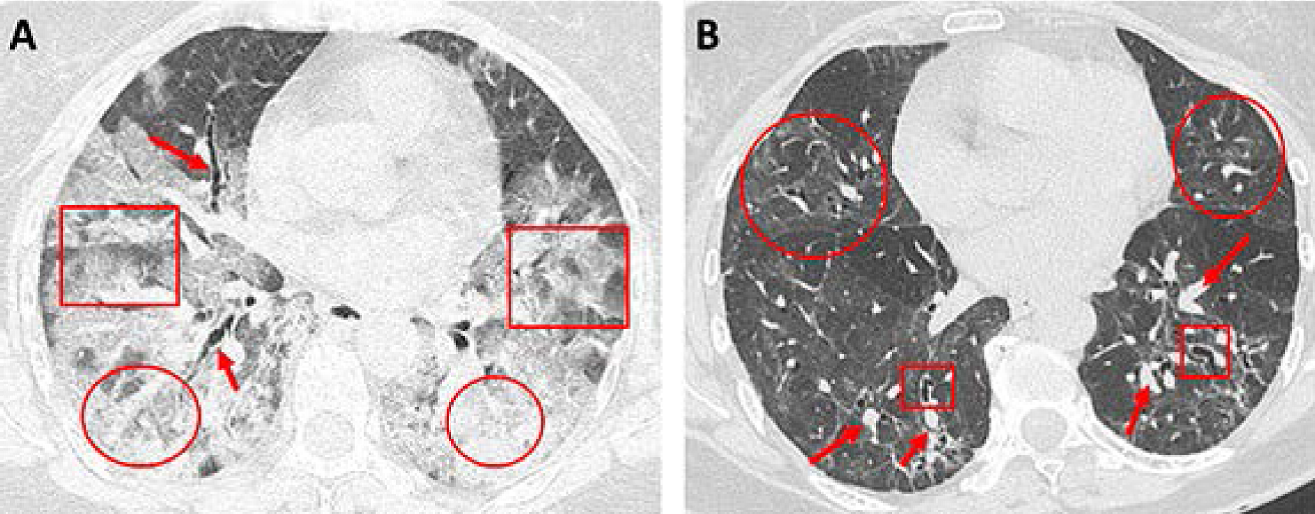

Siguiendo el esquema de monitoreo propuesto, es posible tener una visión oportuna de los cambios que se presentan en el seguimiento de los pacientes. Hemos reportado cómo se ve la modificación de las pruebas de función respiratoria durante los primeros seis meses de seguimiento en una paciente con neumonía grave por COVID-19.57 Claramente se puede apreciar cómo los valores van aumentando a medida que pasan los meses luego de haber iniciado tratamiento con rehabilitación pulmonar y oxigenoterapia durante las primeras semanas de convalecencia (Cuadro 5). Del mismo modo, al inicio de la enfermedad se observan imágenes de consolidación asociada a un patrón en empedrado en la TACAR (Figura 6A); en tanto que a los seis meses, en la TACAR de control es posible observar bronquiectasias de tracción, engrosamiento de septos interlobulillares y tenues infiltrados en vidrio esmerilado ( Figura 6B).

Figura 6. Tomografía axial computarizada de alta resolución (TACAR) en paciente con COVID-19 grave. A) La TACAR realizada durante el cuadro agudo muestra lesiones consolidativas bilaterales posteriores (círculos rojos) con broncograma aéreo en lado derecho (flechas rojas). En ubicación anterior a estas últimas lesiones se aprecian lesiones bilaterales con patrón en empedrado (recuadros rojos). B) La TACAR de control a los seis meses de haber padecido COVID-19 muestra engrosamiento bilateral de septos interlobulillares en regiones posteriores (flechas rojas). También se aprecia dilataciones bronquiales segmentarias aisladas (bronquiectasias, círculos rojos), además de infiltrados en vidrio esmerilado tenues en etapa de regresión (recuadros rojos).